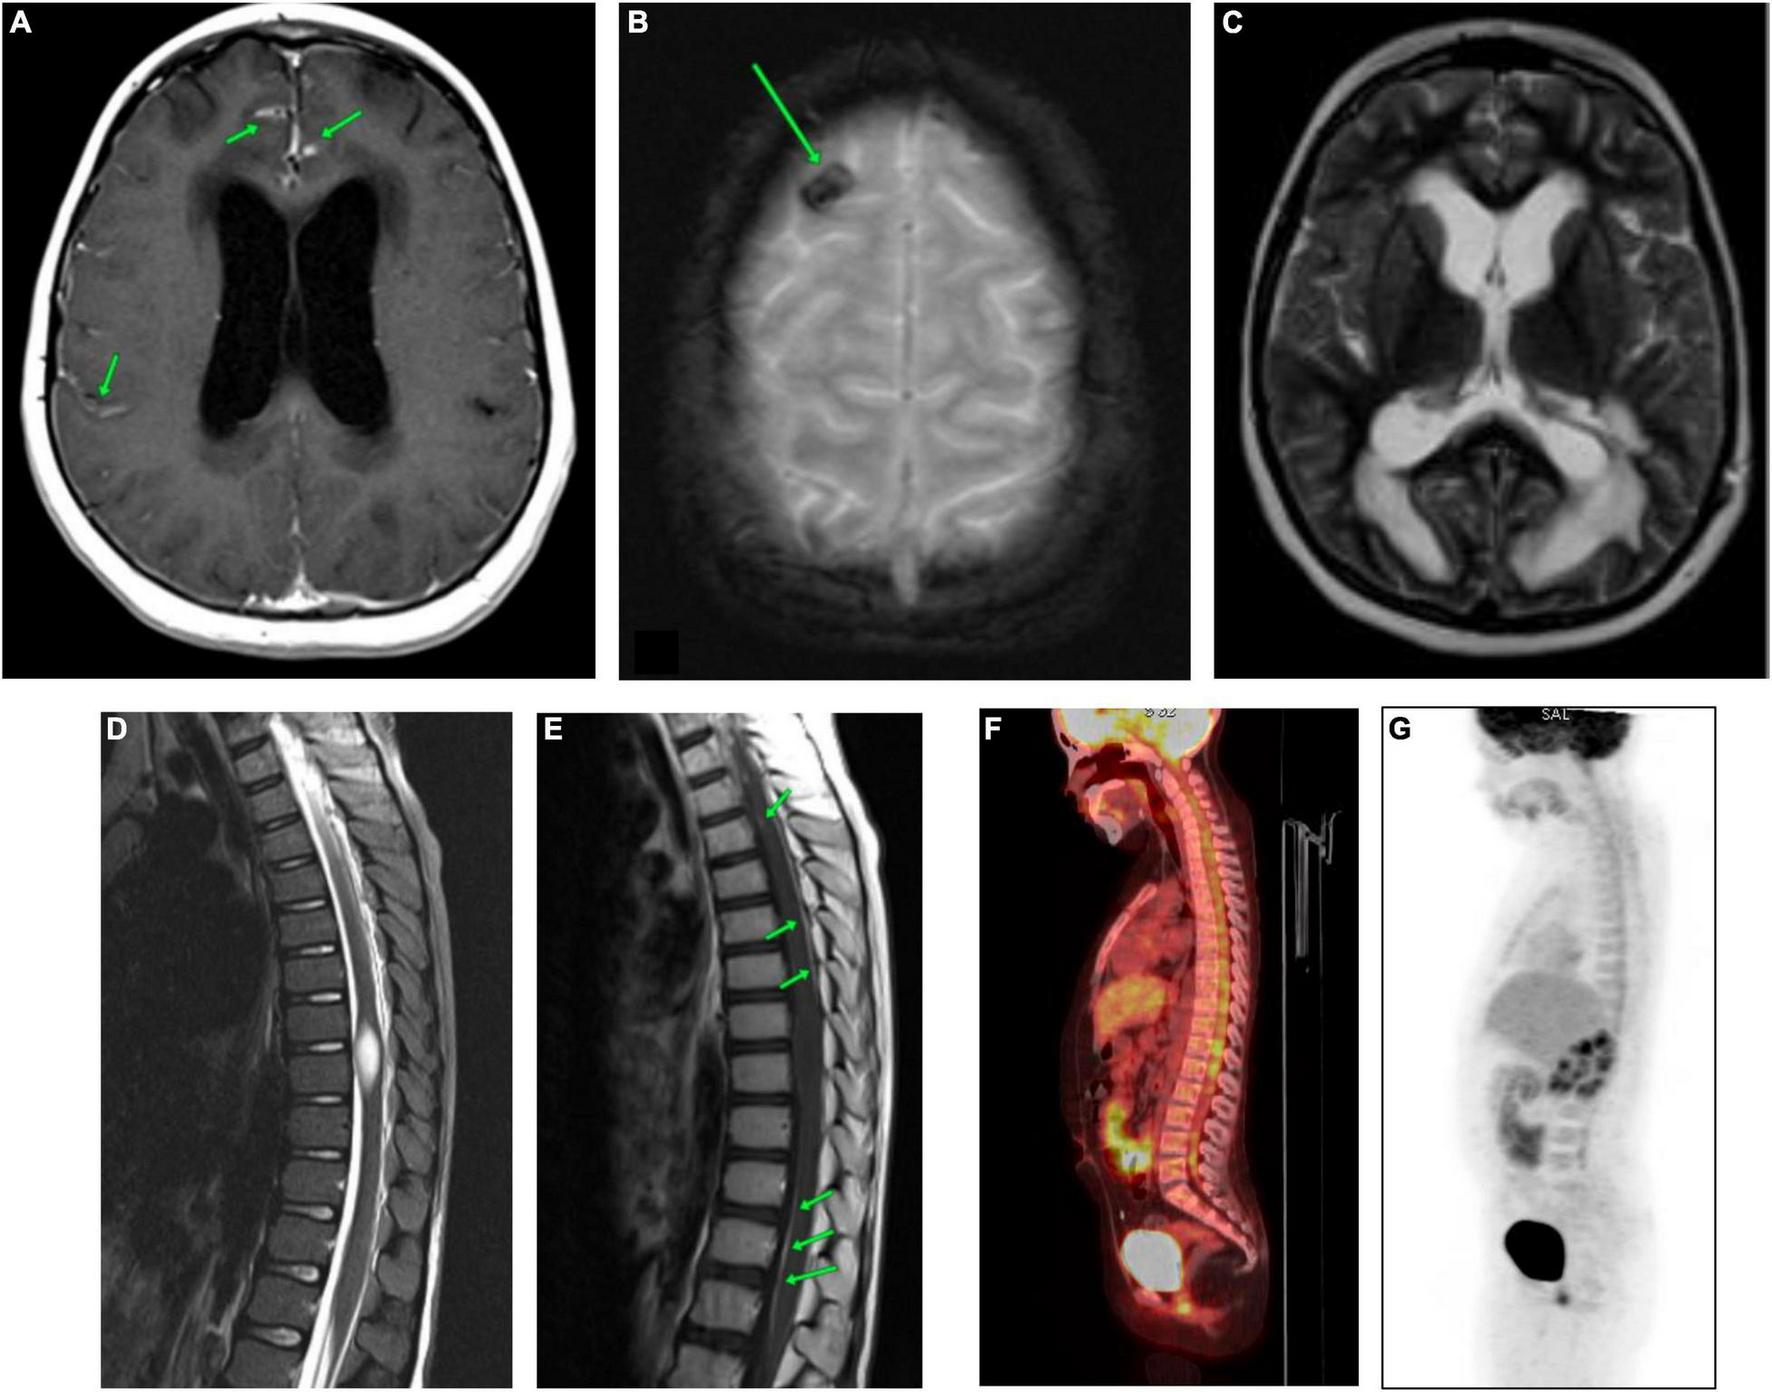

At the time of hospitalization at the Almazov National Medical Research Centre, the patient had moderate asthenic syndrome and ataxia. MRI of the brain and spinal cord showed diffuse infiltration of the pia mater and dura mater of the cerebral hemispheres and posterior cranial fossa (PCF) with irregular thickening and contrast enhancement (Figure 1A and Supplementary Figures 1A,B).

FIGURE 1

CNS MRI and the whole-body PET-CT of the patient carried out at the time of admission to the Almazov National Medical Research Centre. (A) Brain MRI (CE T1-WI). Diffuse infiltration of the meninges (soft and hard) of the cerebral hemispheres with uneven thickening and contrast accumulation. (B) Brain MRI (T2*-WI). The area of hemosiderin deposition in the cortex of the right frontal lobe. (C) Brain MRI (T2-WI). Triventricular hydrocephalus. Ventriculoperitoneal shunting (VPS), the shunt in the left lateral ventricle. Severe periventricular edema. Subarachnoid spaces are narrowed. (D) Spinal cord MRI (STIR). The spinal cord at the level of Th8-Th9 vertebrae is thickened, and a spindle-shaped formation of 22 mm x 9 mm x 8 mm is observed. (E) Spinal cord MRI (post-contrast T1-WI). Pia mater of the thoracic region of spinal cord evenly accumulates a contrast agent. The spindle-shaped formation shows no signs of contrast. (F,G) The whole-body [18F]2-fluoro-2-deoxy-D-glucose positron emission tomography/computed tomography (18FDG-PET-CT). The picture of diffuse heterogeneous hyperfixation of the radiopharmaceutical along the course of the cervical, thoracic, and lumbar segments of the spinal cord with a maximum value of standardized drug capture of 3.12.

Regional edema, cystic transformation, and hemorrhagic impregnation of cerebellar hemispheres, as well as a site of hemosiderin deposition in the cortex of the right frontal lobe, were visualized (Figure 1B and Supplementary Figures 2A,B). Symmetrical expansion of the lateral ventricles and III ventricle, as well as severe periventricular edema, was detected, while the subarachnoid spaces were narrowed (Figure 1C and Supplementary Figure 3).

In the spinal cord, a spindle-shaped lesion with the size of 20 mm × 9 mm × 8 mm (Figure 1D and Supplementary Figure 4) at the level of Th8-Th9 vertebrae was revealed, with hyperintense MR signal on T2-WI and STIR and without contrast enhancement (Figure 1E), which has been regarded as myelitis. The contrast enhancement by the pia mater was noted throughout the thoracic spinal cord (Figure 1E). Repeated CSF cytology was normal.

The whole-body [18F]2-fluoro-2-deoxy-D-glucose positron emission tomography/computed tomography (18FDG-PET/CT) allowed to reveal diffuse heterogeneous hyperfixation of the radiopharmaceutical along the cervical, thoracic, and lumbar spinal cord segments with a maximum standardized uptake of 3.12. This PET-CT picture was non-specific and could be observed in both tumor lesions and inflammatory processes (Figures 1F,G).